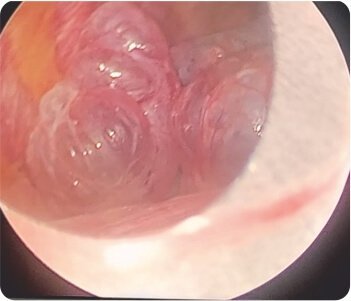

In view of the risk of recurrent pneumothorax, the patient was taken up for VATS (Video Assisted Thoracoscopic Surgery) with right sided bullectomy was done. During the hospital stay, the patient was closely monitored and the patient’s condition gradually improved and was discharged after being stabilized.

Video-assisted thoracoscopic surgery during procedure